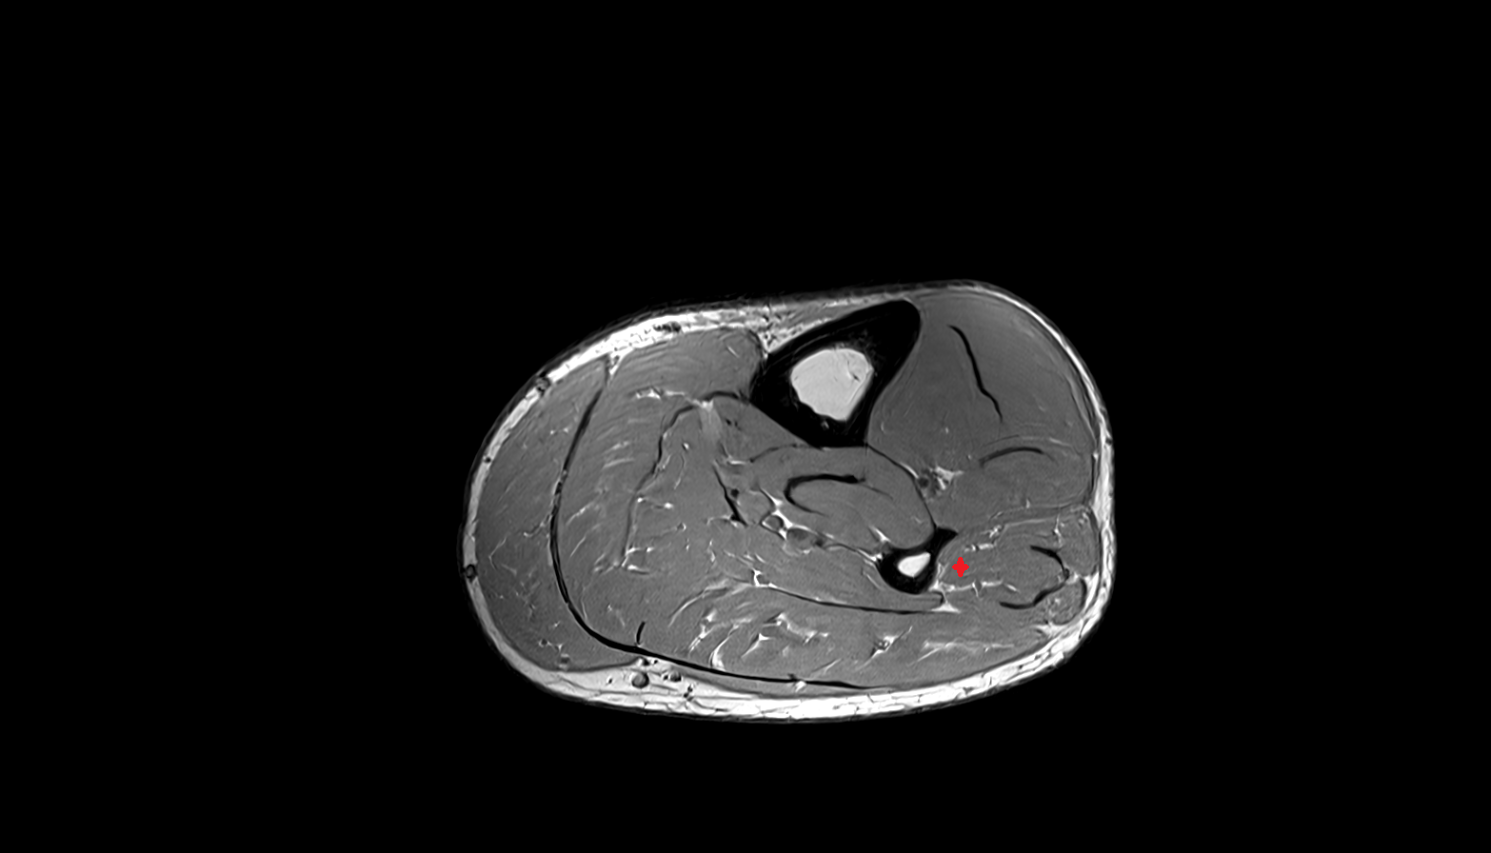

- Tibialis posterior muscle

- Flexor digitorum longus muscle

- Flexor hallucis longus muscle

- Tibialis posterior tendon

- Achilles tendon

- Extensor digitorum longus muscle

- Tibialis anterior muscle

- Fibularis longus muscle (peroneus longus muscle)